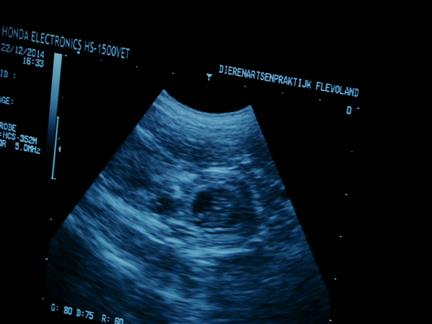

| 22 december 2014, eindelijk is het dan zo ver, 28 dagen na de dekking, dus tijd voor de echo om te kijken of Fleur drachtig is |

| na het scheren ligt Fleur braaf op haar rug, met onze dochter aan de ene kant en de assistente aan de andereke kant, en dan de eerste beelden, wat een mooi gezicht :-) |

niet alle foto's zijn even duidelijk |

| maar in de donkere ronde vlekken |

zie je witte lijntjes |

| en dat zijn .......... de puppies :-) |

ook zijn de hartjes al aan het kloppen, allemaal prachtig om te zien |